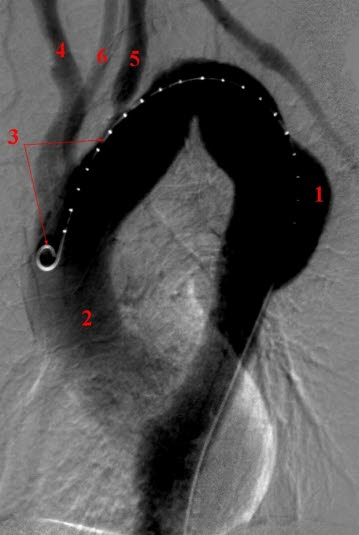

Aneurisme i thoracale aorta descendens.

- Aneurismet (utposning) av aorta descendens

- Aorta ascendens

- Kateter

- Truncus brachiocephalicus

- A. subclavia sinister

- A. carotis communis sinister